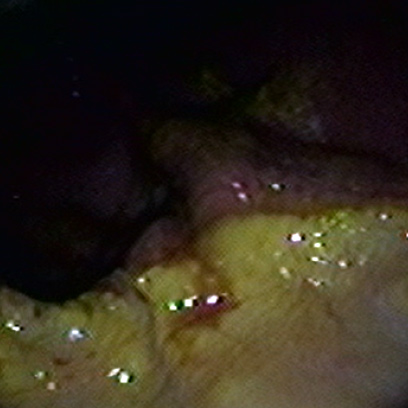

¿CUÁNDO DERIVA EN

ÚLCERA GÁSTRICA?

Cuando la irritación e inflamación gástrica en equinos progresa, la mucosa del estómago se erosiona y puede desarrollar una úlcera gástrica o lesión ulcerativa.